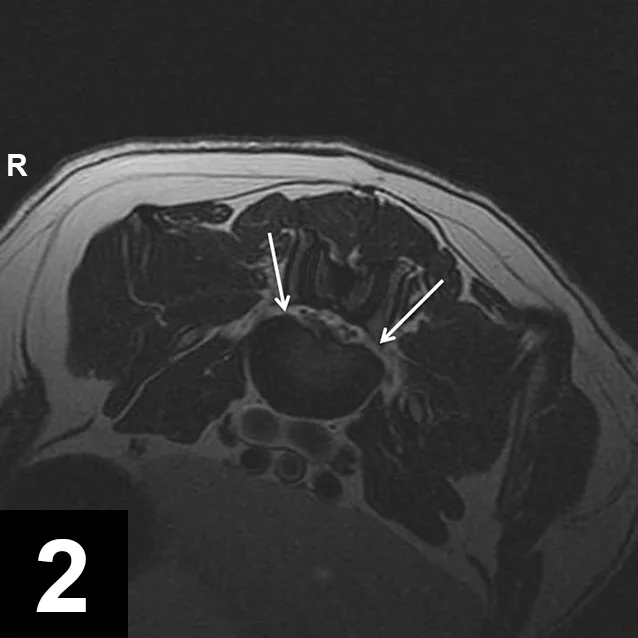

• Complete spinal MRI revealed multifocal intervertebral disc degeneration throughout the mid-thoracic, caudal thoracic, and lumbar vertebral column, with intervertebral disc herniation resulting in mild spinal cord compression at T13–L1, L1–L2, L2–L3, L5–L6, and L6–L7 (Figure 1). The L7–S1 intervertebral disc was also herniated, leading to severe bilateral nerve root compression at this location (Figure 2). The discs in the cervical and cranial thoracic spine were adequately hydrated.

Figure 2

Axial T2 image of the lumbosacral junction showing bilateral nerve root compression (white arrows)